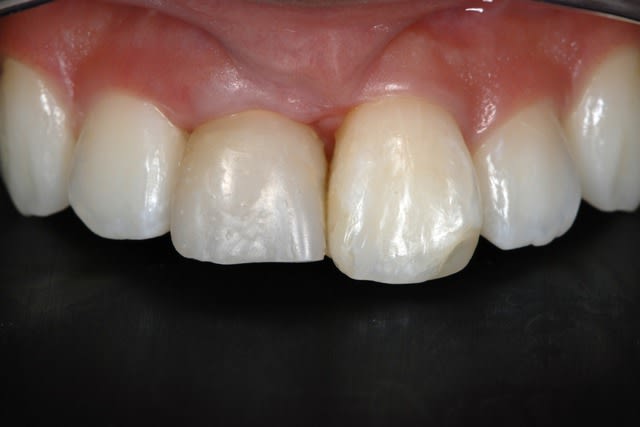

Même si ce n'est pas le top de l'esthétique, ta phase provisoire est déjà gérée ! Pourquoi alors prendre des risques en faisant une mise en esthétique immédiate ??

D'accord pour le rouleau lors de la pose. Et si ce n'est pas suffisant, tu peux en remettre une couche lors de la mise en fonction. Faire une belle provisoire avec un beau profil d’émergence pour guider le cicat et le tour est joué !!

Mise en esthétique immédiate + conjonctif enfoui si tu veux gagner en vest. provisoire avec super profil d'emergence pour choisir facilement son pilier apres.

Si bonne stabilité I, pas plus de risque que sans prov. et bien plus predictible pour l'esthétique, moins chère, moins de rdv, moins d'anesthesie, patient plus content.